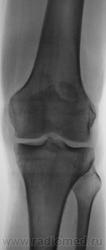

Без костных травматических изменений.

Мужчина 39 лет, жалоб нет. Обратил внимание на разницу с другим коленным суставом (выпирает). Второй сустав на снимке без изменений. Травм утверждает, что не было.

Получается просто удвоение наколенника ....не попадалось